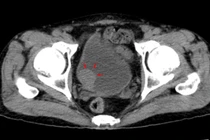

Ung thư bàng quang là bệnh lý đứng thứ hai sau ung thư tiền liệt tuyến thuộc hệ tiết niệu sinh dục và thứ 4 trong các loại ung thư phổ biến. Siêu âm là phương pháp dễ dàng nhìn được hình ảnh khối u, rẻ tiền, không xâm lấn.